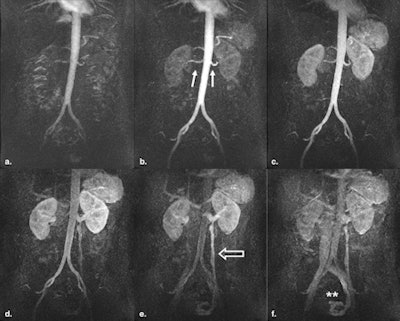

| Six consecutive coronal maximum-intensity projection images from a 3D time-resolved contrast-enhanced MRA of a 43-year-old woman presenting with secondary arterial hypertension. The suprarenal and infrarenal abdominal aorta, as well as the renal arteries (b, white arrows) are clearly delineated. In the venous phase, an insufficiency of the left ovarian vein (e and f, open arrow) was found as a secondary finding. Image courtesy of Academic Radiology. |